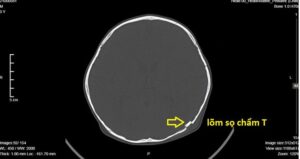

Theo bác sĩ, trẻ em xương yếu, nếu bị chấn thương vùng đầu, sau đó [...]